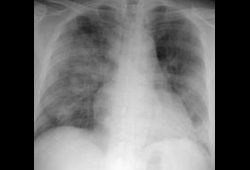

- გულმკერდის რენტგენოგრაფია (რენტგენი)